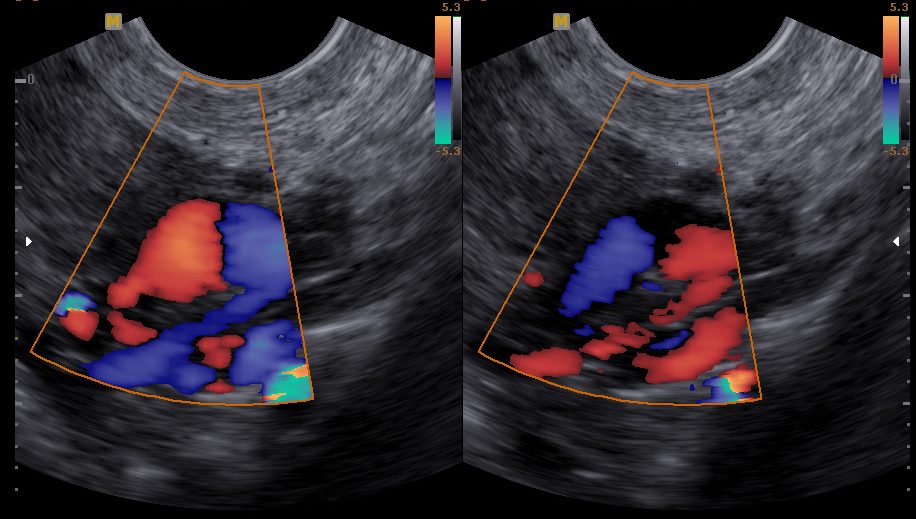

Imagem de ultrassonografia transvaginal demonstrando veias uterinas dilatadas e com mudança na direção do fluxo durante manobras provocativas, confirmando o diagnóstico de Varizes Pélvicas.